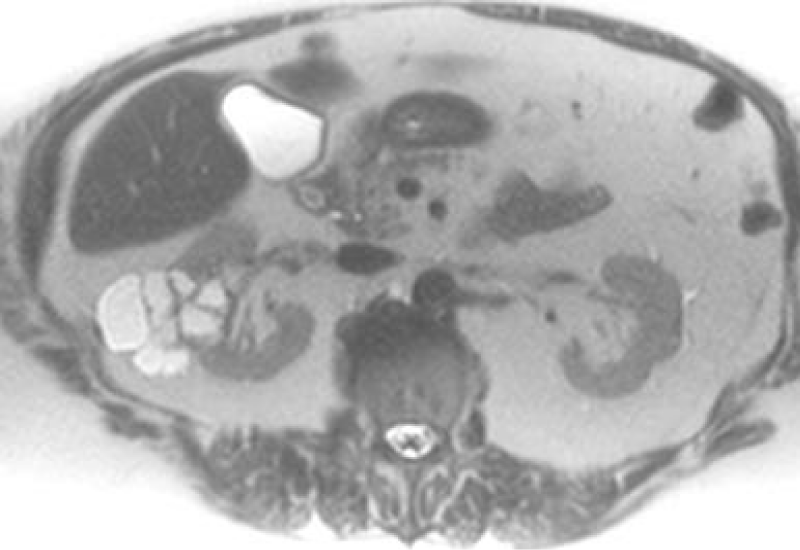

Initial diagnoses and staging are most commonly done with abdominal Computed Tomography (CT), Magnetic Resonance Imaging (MRI) (Figure 1) and Ultrasound (US) are also frequently used. This is due to CT’s ability to detect up to 90% renal masses including SRM, and its higher spatial resolution compared to the MRI. CT can distinguish benign from malignant lesions hence avoiding further testing and detecting surrounding lymphadenopathy or thrombi (Figure 2), has rapid image acquisition rates, is compatible with metallic medical devices, and can obtain high-resolution enhancement measurements using the Hounsfield unit (HU [1-3,5].

Figure 2: Right renal Clear Cell RCC with right Renal Vein thrombus.